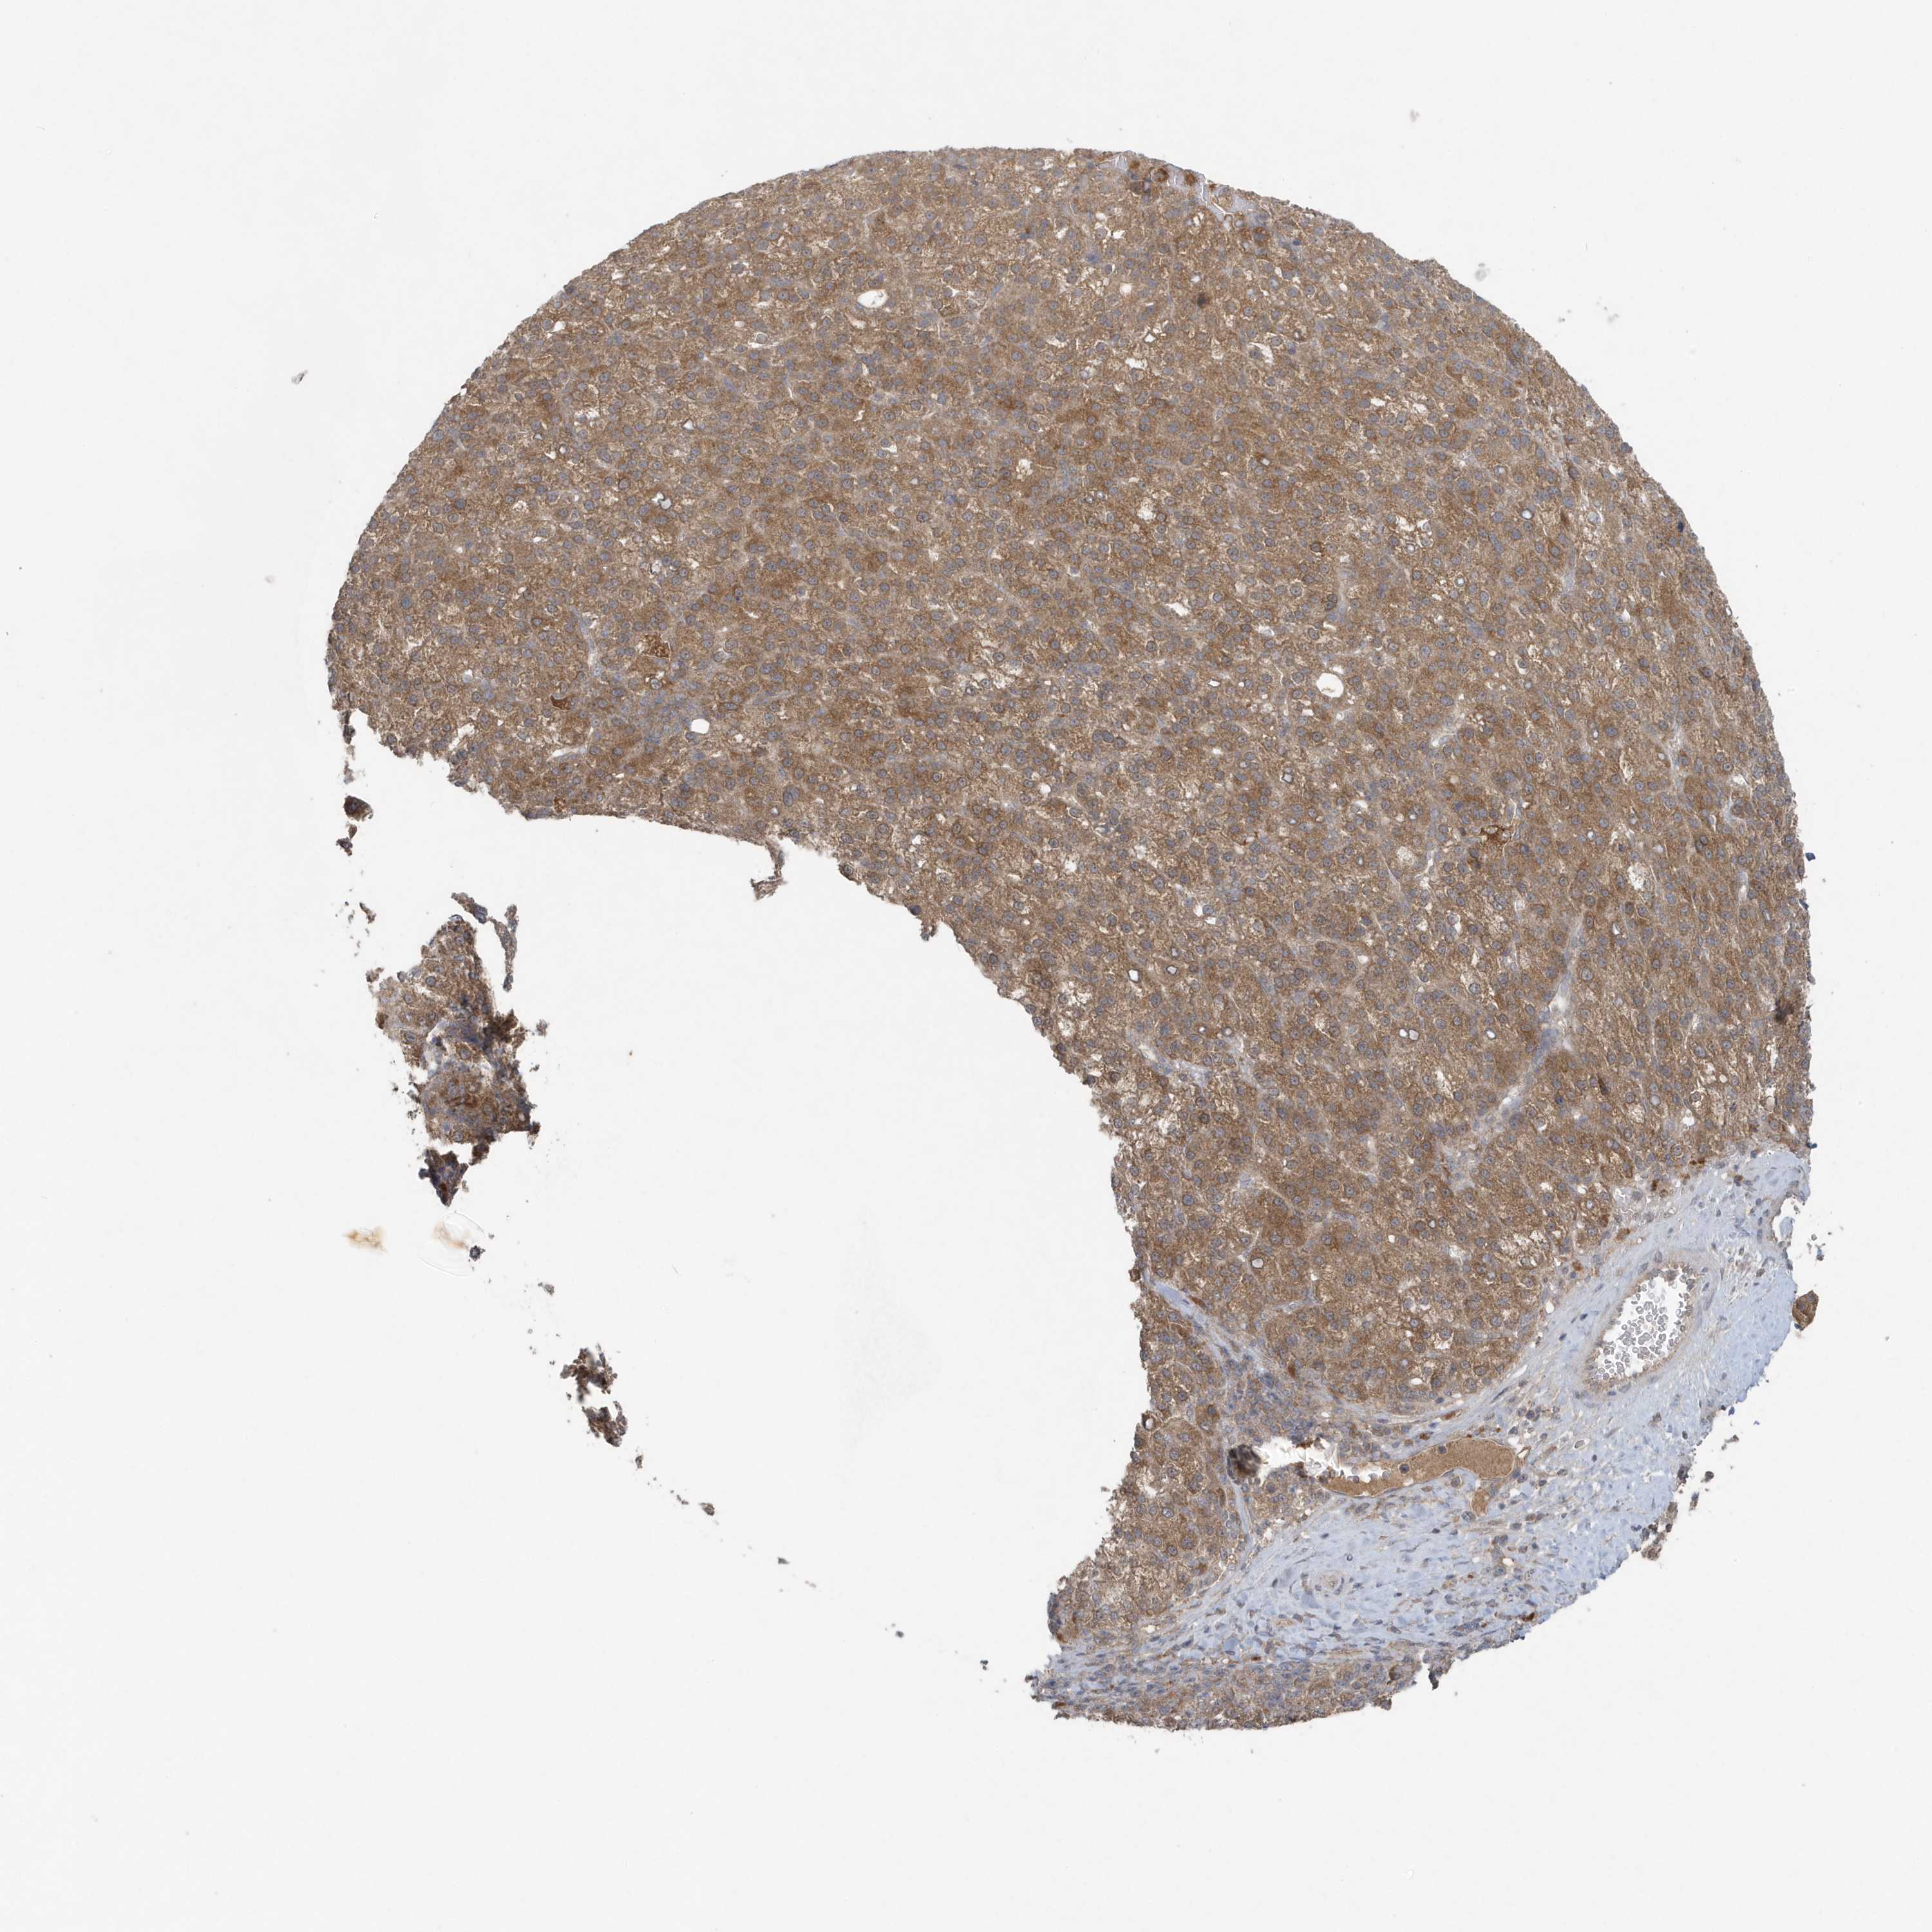

LIVER CANCER - Protein expressioni

A mouse-over function shows sample information and annotation data. Click on an image to view it in a full screen mode. Samples can be filtered based on level of antibody staining by selecting one or several of the following categories: high, medium, low and not detected. The assay and annotation is described here.

Note that samples used for immunohistochemistry by the Human Protein Atlas do not correspond to samples in the TCGA dataset.

Antibody stainingi

Antibody staining in the annotated cell types in the current human tissue is reported as not detected, low, medium, or high, based on conventional immunohistochemistry profiling in selected tissues. This score is based on the combination of the staining intensity and fraction of stained cells.

Each image is clickable and will lead to virtual microscopy that enables deeper exploration of all samples and also displays staining intensity scores, fraction scores and subcellular localization as well as patient and tissue information for each sample.

Antibody HPA011338

Antibody CAB026172

Staining

High

Medium

Low

Not detected

Intensity

Strong

Moderate

Weak

Negative

Quantity

>75%

75%-25%

<25%

None

Location

Nuclear

Cytoplasmic/membranous

Cytoplasmic/membranous,nuclear

Cholangiocarcinoma

Carcinoma, Hepatocellular, NOS